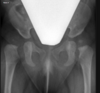

Masculino, 12 anos

Síndrome da sincondrose isquiopúbica assimétrica (Doença de Van Neck-Odelberg)

Variante da normalidade (em geral assintomático)

Crianças

Alargamento e radioluscência na sincondrose isquiopúbica, que simula neoplasias, infecção;